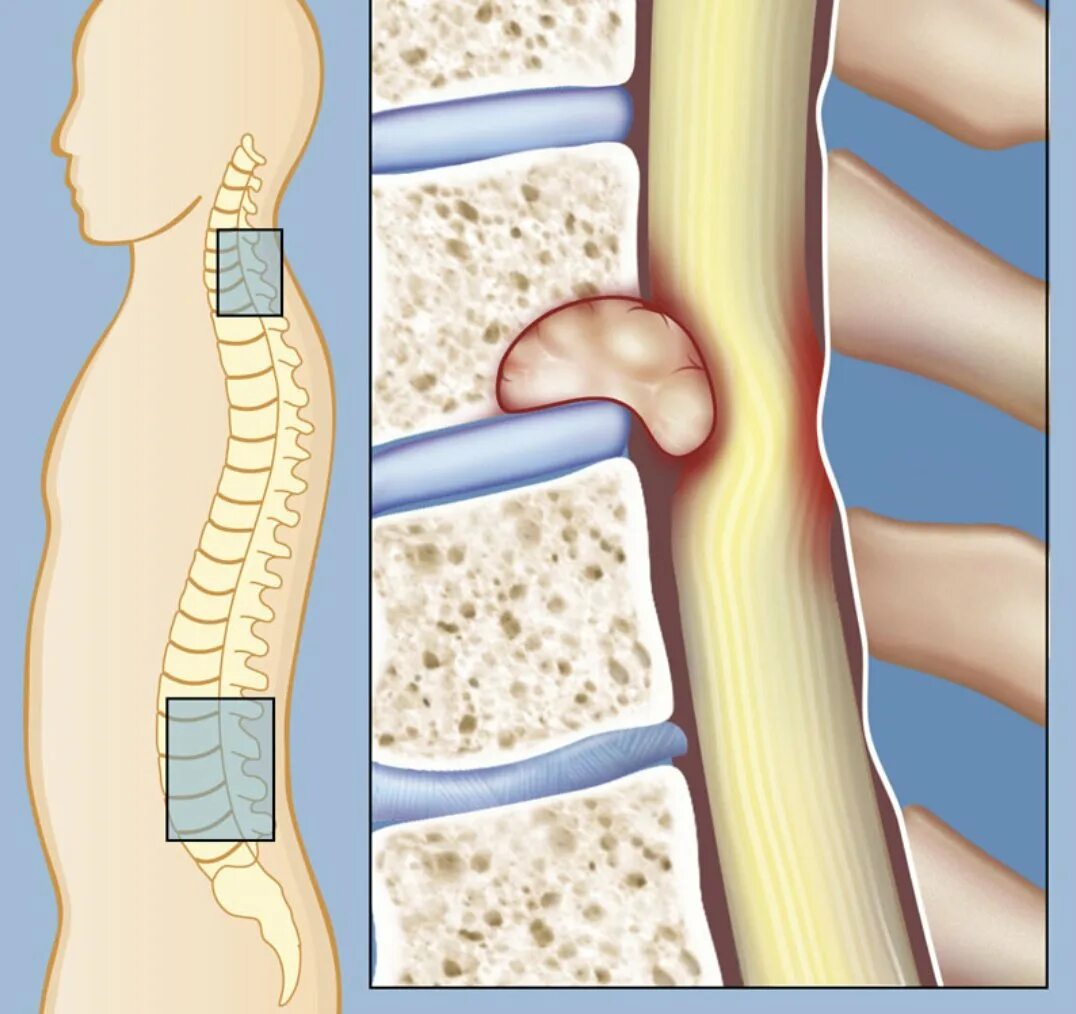

4 стадия метастазы позвоночника